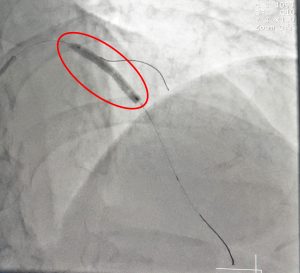

BVXA – BÁO ĐỘNG ĐỎ, ĐẶT STENT MẠCH VÀNH NGHẼN, CỨU SỐNG BỆNH NHÂN BỊ NHỒI MÁU CƠ TIM NGUY KỊCH

Ngày 02/5/2017 vừa qua, Bệnh Viện Đa Khoa Khu Vực Hóc Môn (BV. Hóc Môn) cùng với Bệnh Viện Đa Khoa Xuyên Á (BVXA) đã thực hiện quy trình báo động đỏ liên viện. Bởi đó nhanh chóng cứu sống người bệnh nhồi máu cơ tim cấp trong tình trạng nguy kịch – nhờ phương […]